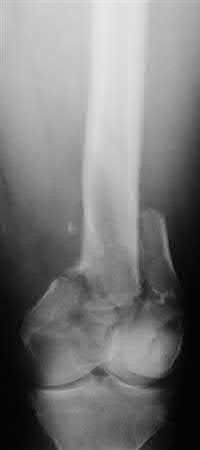

Buttress plating is most appropriate in which of the following clinical situations?

Figure A

Figure B

Figure C

Figure D

Figure E

Buttress plating is appropriate for a Shatzker Type I (see illustration C), as it can prevent collapse and axial deformity from shear or bending forces.

Figure B demonstrates an isolated medial femoral condyle fracture. Lateral locked plating is not an appropriate technique for this fracture.

The fracture shown in Figure B is an AO B type (partial articular fracture). This fracture is best treated with open reduction internal fixation through a medial approach, with lag screw and buttress plate fixation.

Figures A, C, D and E show supracondylar distal femur fractures that can be treated with ORIF with a fixed-angle device such as lateral locked plating.